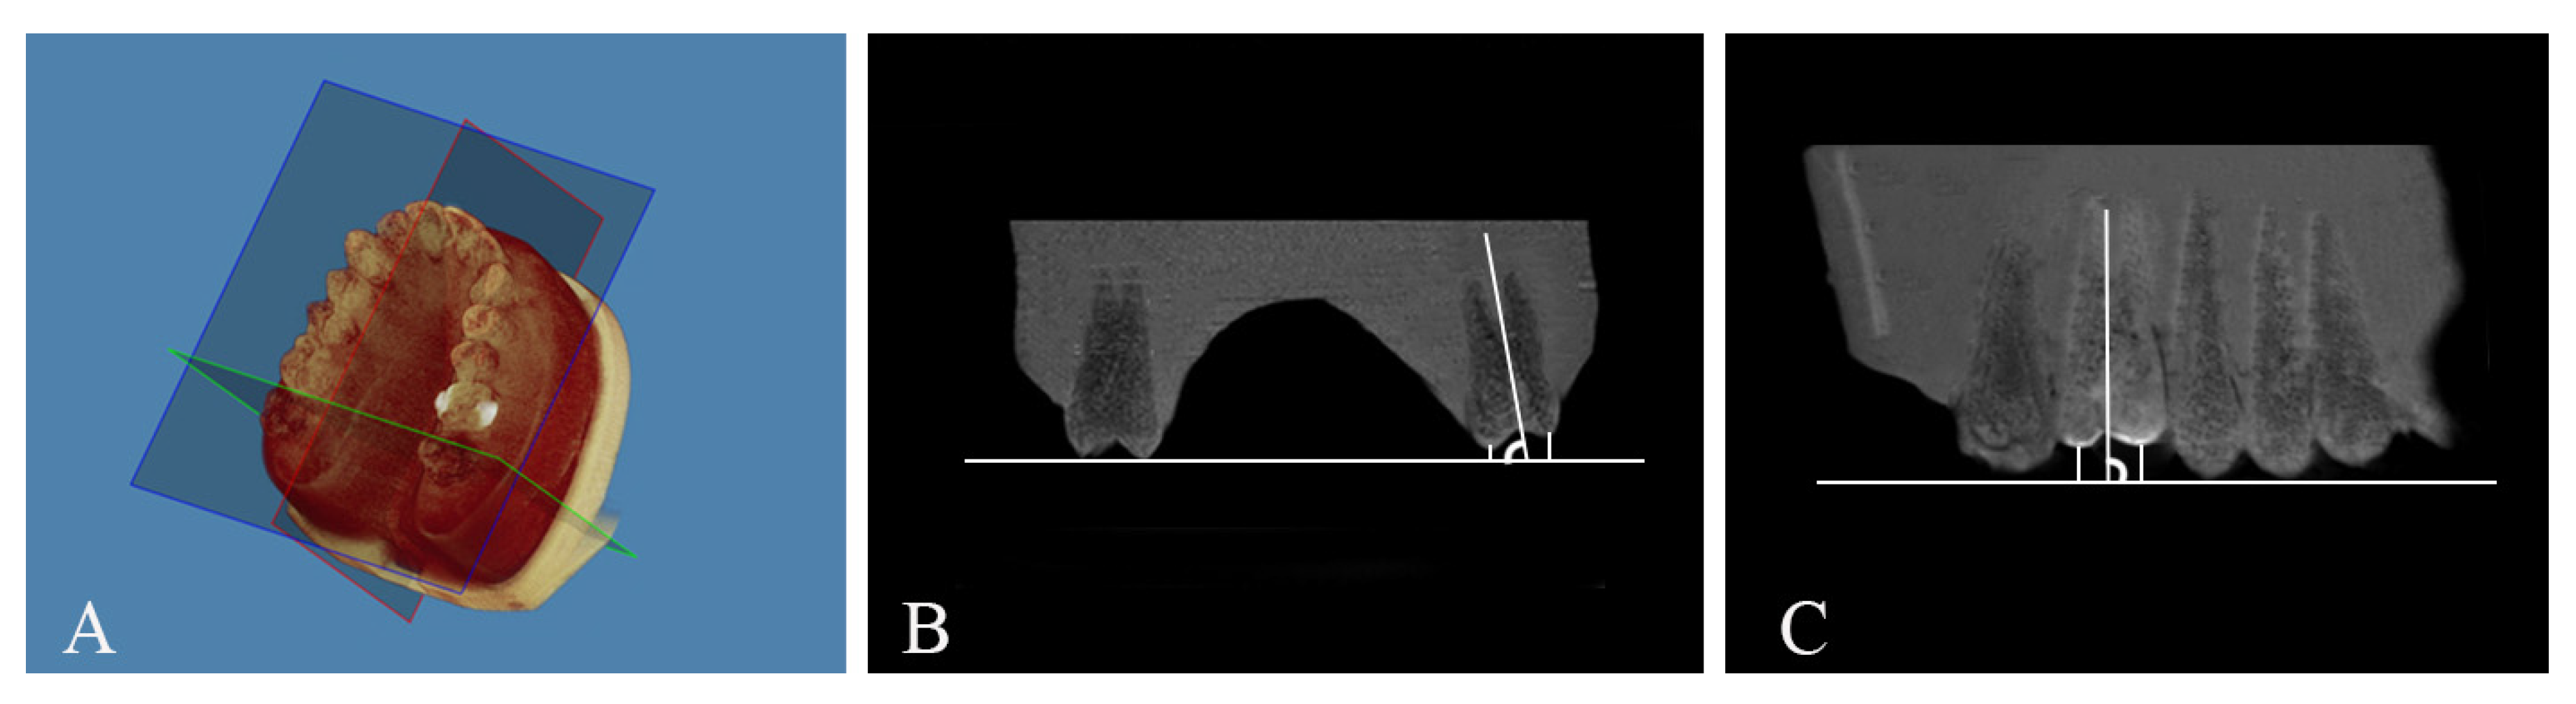

2. Materials and Methods

| Measurements | Definition |

|---|---|

| Ext PC | The distance (mm) between the palatal cusp (PC) and the occlusal plane, measured from the coronal section. |

| Ext BC | The distance (mm) between the buccal cusp (BC) and the occlusal plane, measured from the coronal section. |

| Ext MBC | The distance (mm) between the mesiobuccal cusp (MBC) and the occlusal plane, measured from the sagittal section. |

| Ext DBC | The distance (mm) between the distobuccal cusp (DBC) and the occlusal plane, measured from the sagittal section. |

| BL Tip angle | The buccolingual (BL) angle (degree) between the long axis of the upper left first molar to the occlusal plane, measured from the coronal section. |

| MD Tip angle | The mesiodistal (MD) tip angle (degree) between the long axis of the upper left first molar to the occlusal plane, measured from the sagittal section. |